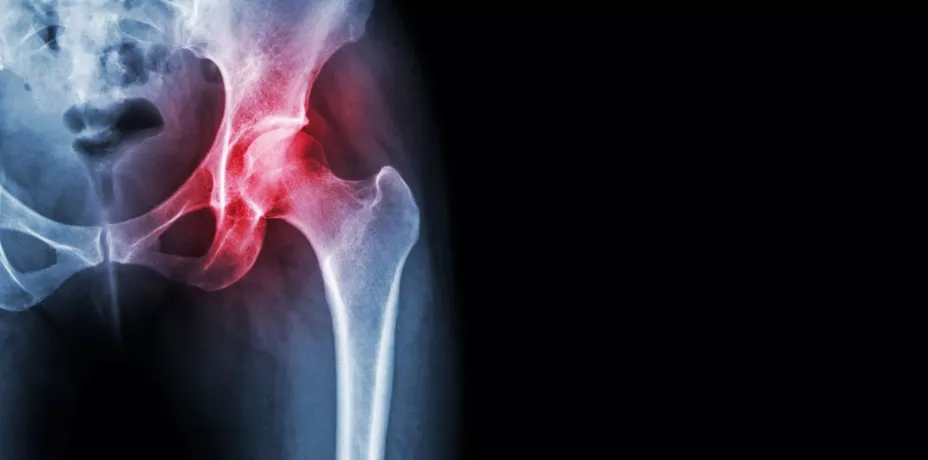

Con esta vitamina se logra alcanzar el pico de masa ósea; sobre todo en la segunda década de vida, para lograr que en los momentos de pérdida de densidad acelerada, como en el caso de la menopausia o el envejecimiento, tengamos una reserva de huesos suficiente para evitar osteoporosis.

El doctor Israel Macías Hernández, especialista en Medicina de Rehabilitación, resalta que el consumo de vitaminas y minerales es necesario diariamente y más cuando se realiza alguna actividad física. “El aporte suficiente de Vitamina D ayuda a fijar el calcio dentro del tejido óseo; lo cual favorece a los deportistas evitando lesiones, haciéndolos más resistentes y menos propensos a fracturas'”, agregó.